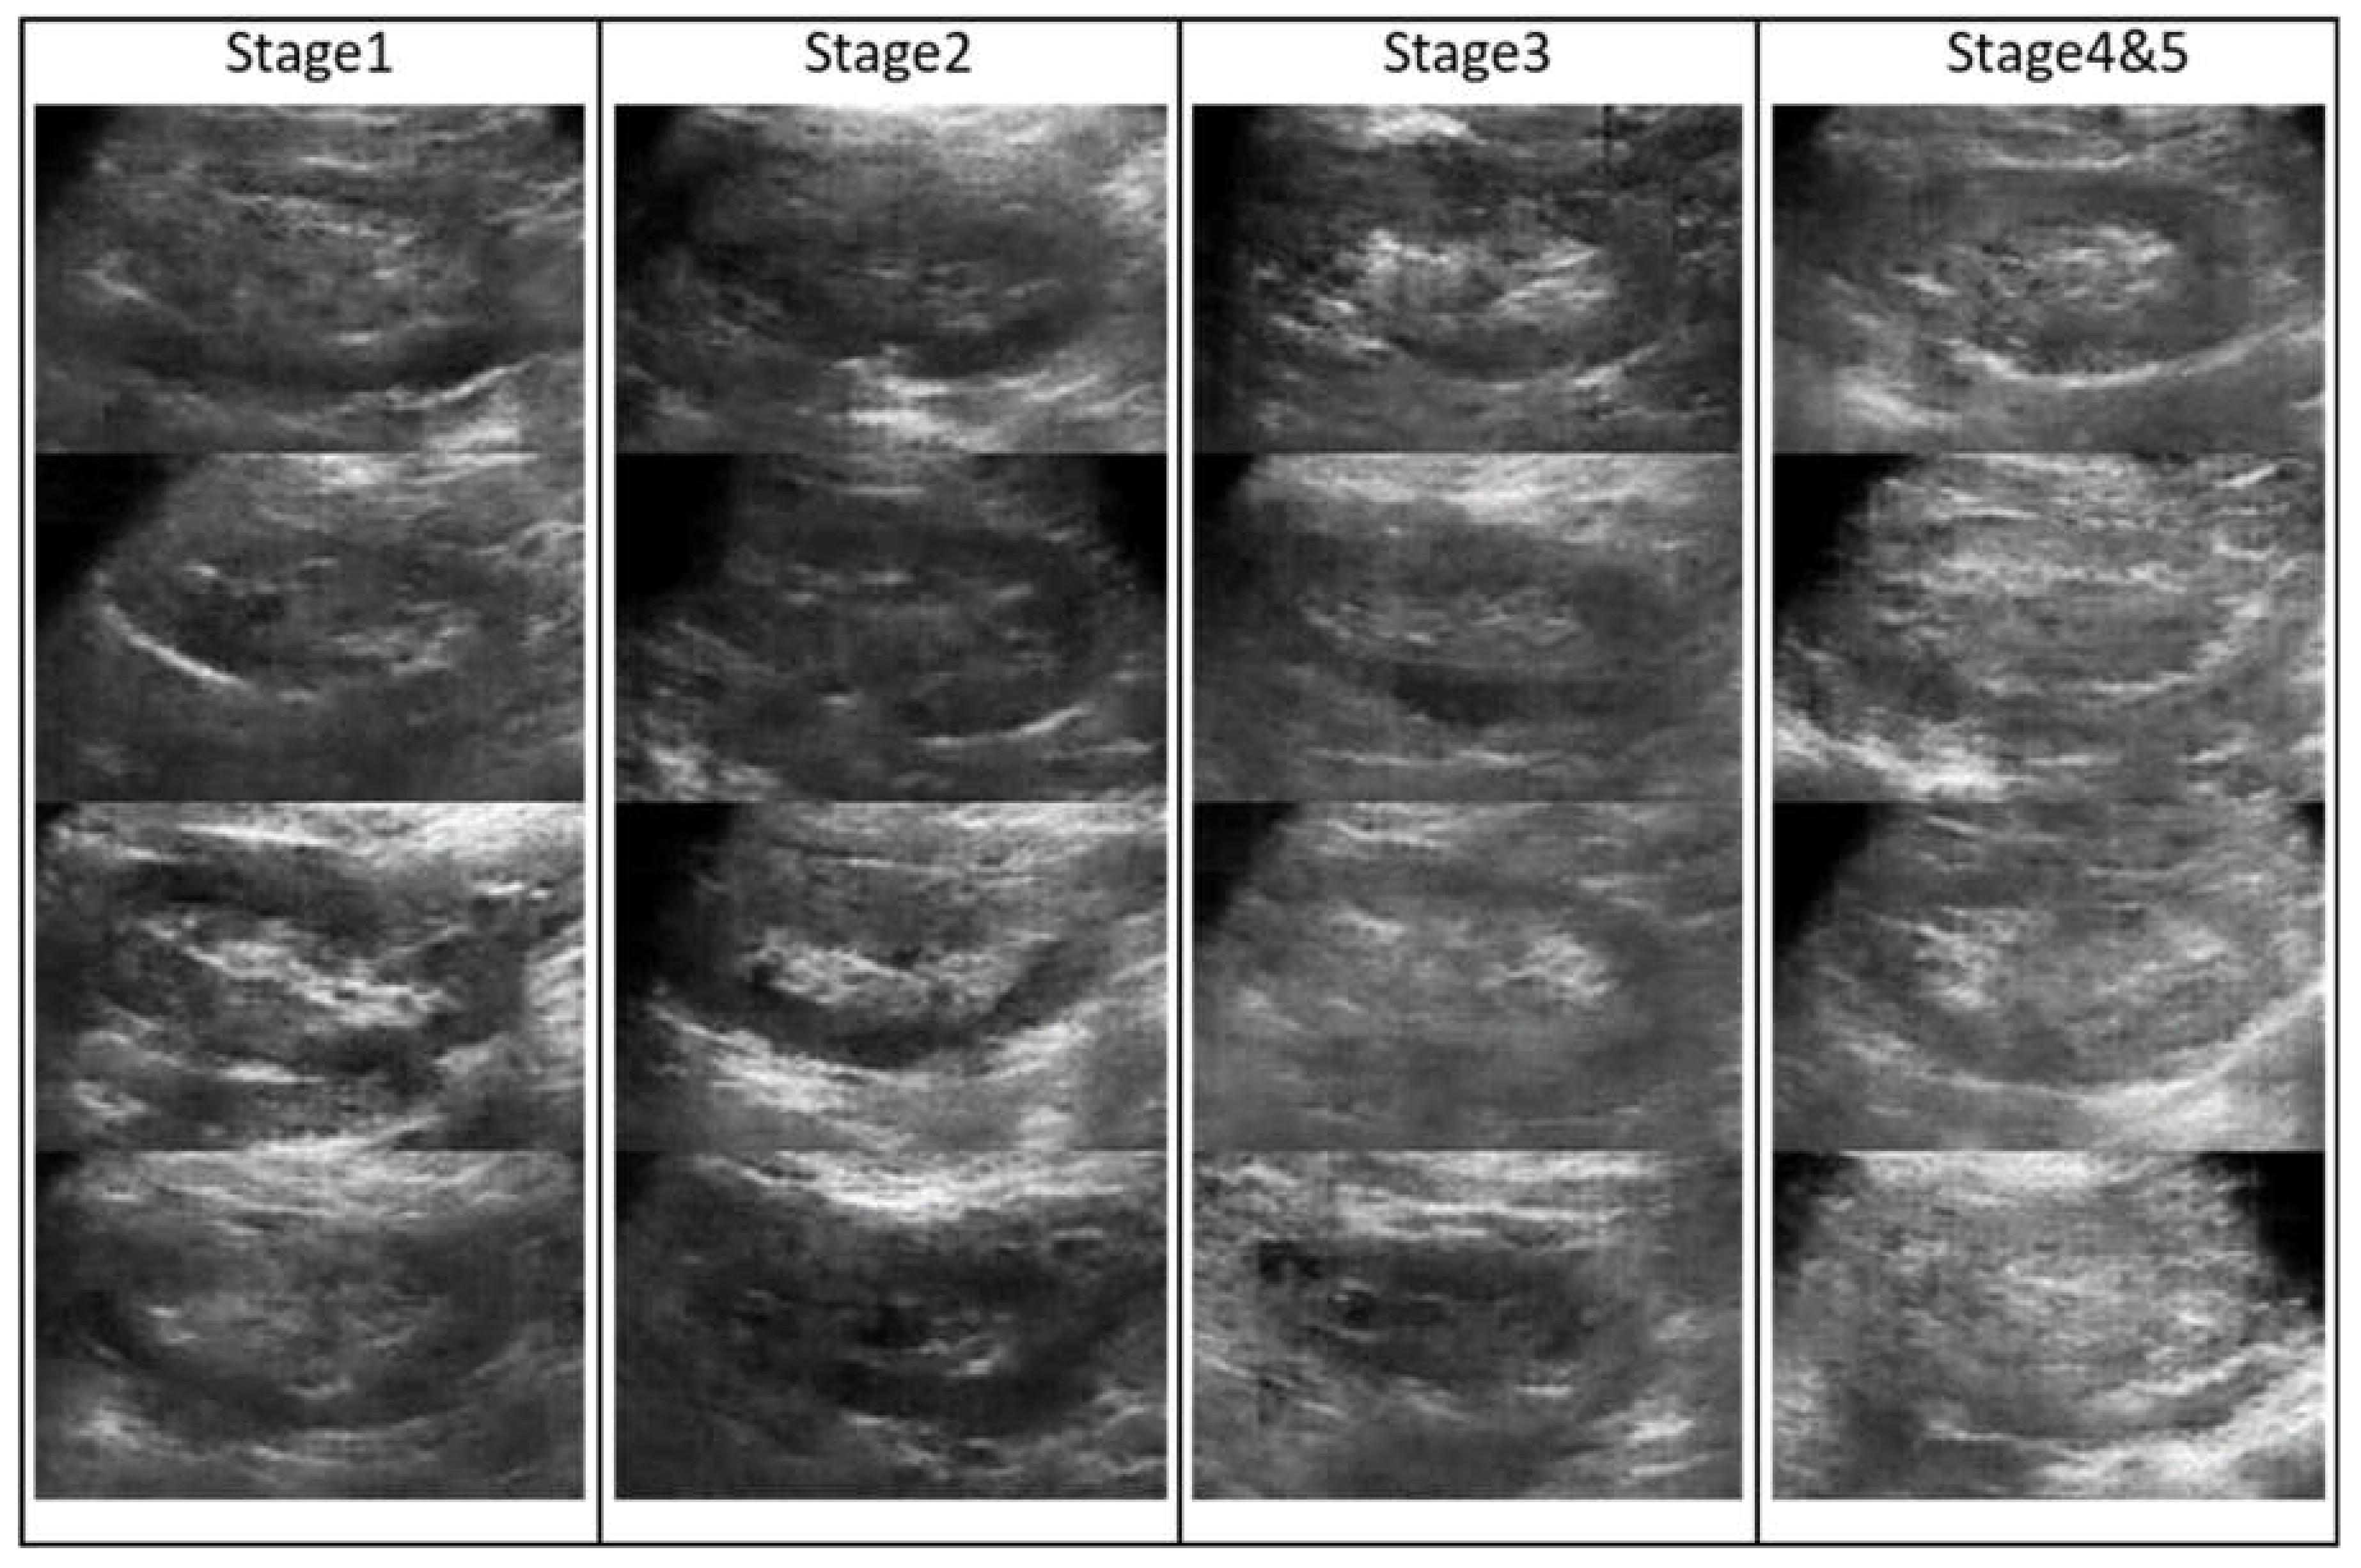

2 for five different CKD stages. According to the settings, from the first to the fifth CKD stage, the remaining ultrasound images contained 231, 134, 91, 108, and 43 images, respectively [

35]. However, the number of images in the fifth stage was relatively small; we combined the fourth and fifth stages into the fourth stage and represented it as a serious condition stage. Several examples of kidney images are shown in

Figure 1. From the left to right columns, the images were diagnosed from the first to the fourth categories.